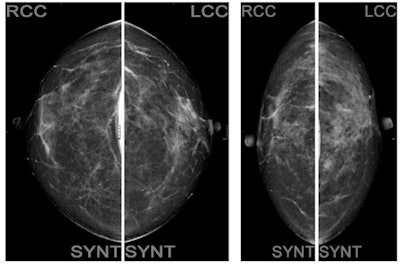

The women were divided into two groups. The first group included 15 women undergoing standard protocol with standard configuration for the automatic exposure control (AEC) algorithm present on the mammography unit, including eight projections: four with digital mammography that included the breast implant and four with tomosynthesis (with synthetic image) using the Eklund maneuver, a modified compression technique that can be used for patients with augmented or reconstructed breasts postmastectomy.

In a second group of 38 women, a low-dose configuration of the AEC was activated to ensure a low-dose protocol.

If the Eklund maneuver is also performed in tomosynthesis mode, the woman is exposed to an average of 11 mGy in total. A low-dose configuration of the AEC is associated instead with an average glandular dose equal to 9.2 mGy total. This configuration allowed a maximum amount of radiographic information currently possible, lowering the dose by 15%, while maintaining adequate image quality, they pointed out.

"At the present time, tomosynthesis for the study of breasts with implants is not considered a valid diagnostic test, mainly due to the encumbrance of the prosthesis. However, the results of this test seem to highlight the possibility to use it effectively," the authors concluded.